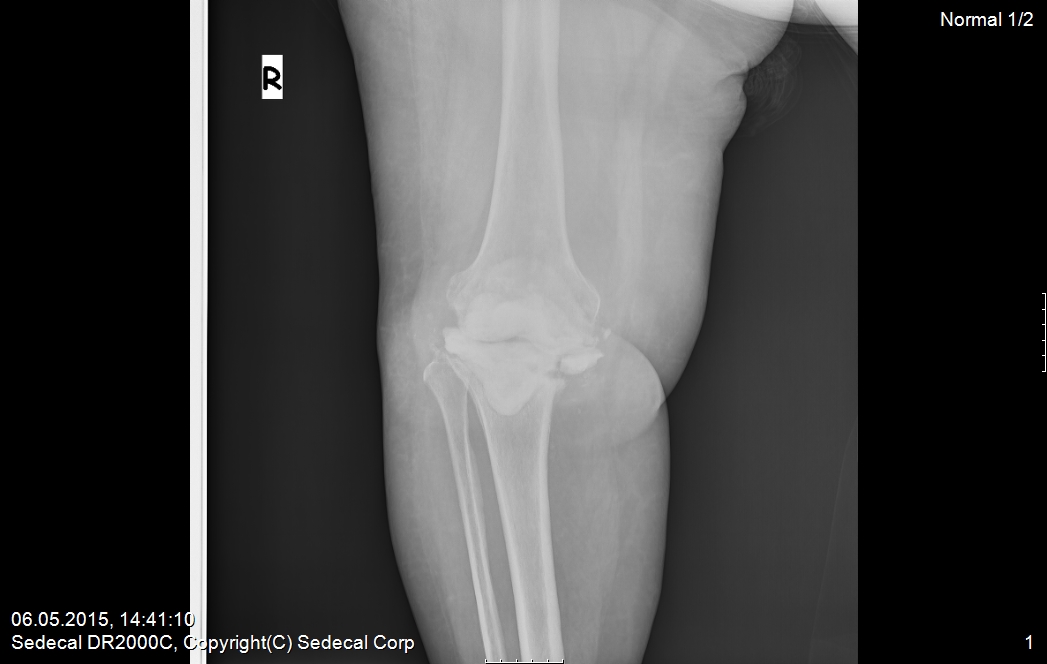

gevşemiş iltihaplı diz protezi 1.

gevşemiş iltihaplı diz protezi 2